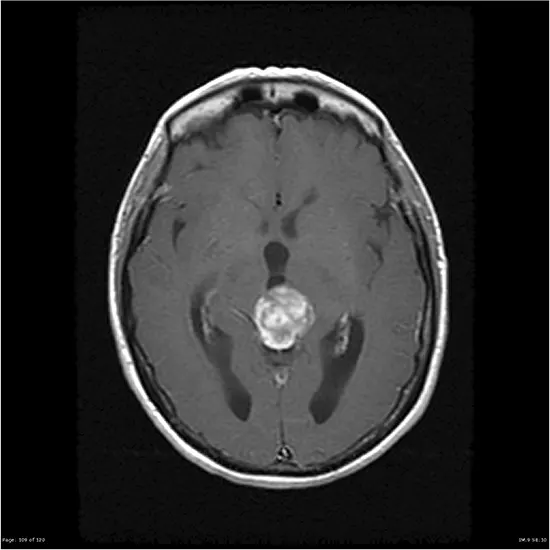

Pineal astrocytoma is a rare type of brain tumor that originates from astrocytes, which are a type of glial cell in the brain. The pineal gland is a small pinecone-shaped gland located deep within the brain, and pineal astrocytomas specifically arise in this region. Pineal astrocytomas are considered a type of glioma, which are tumors that arise from glial cells.

Diagnosis of pineal astrocytoma usually involves a combination of medical history, physical examination, neuroimaging studies (such as MRI or CT scan), and a brain biopsy for definitive diagnosis. Molecular testing for specific genetic mutations may also be performed to further characterize the tumor.